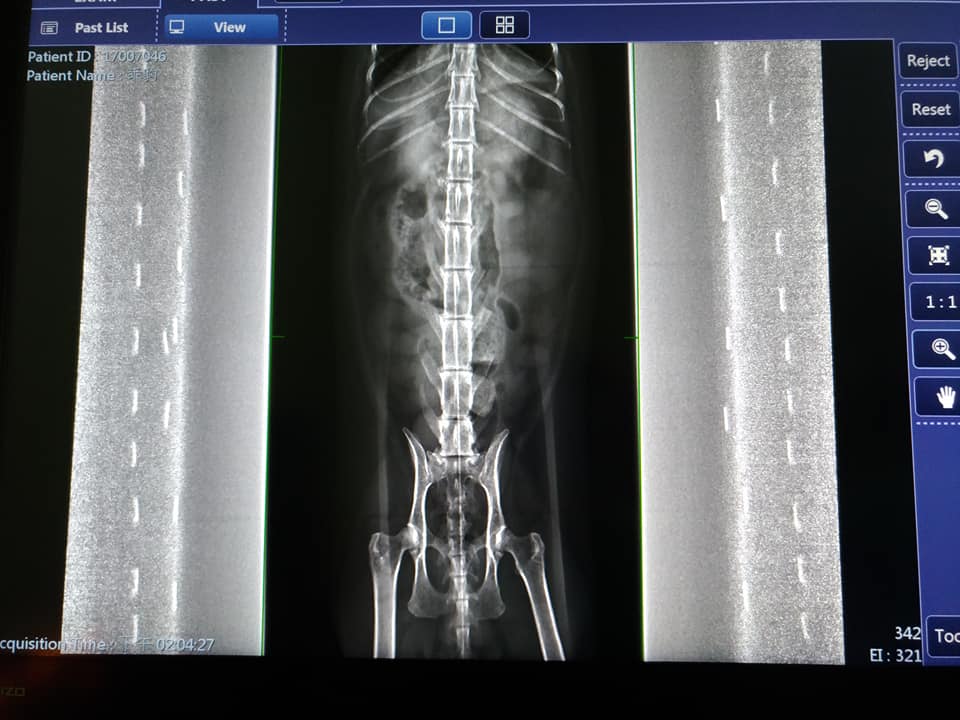

10/21 澄諾初診 乖豹 4.71KG

照X光,只有發現髖關節跟腰間椎有退化的狀況。

如果腰間椎要做更詳細的檢查,可以去台大做核磁共振,

但依照台大核磁共振的設備來說,目前是最低階的,所以醫師對這部分能否更詳細的顯現表示存疑。

關節退化有可能會導致乖豹走路會痛,進而不去使用腳而造成肌肉痿縮,所以不是神經方面的問題。